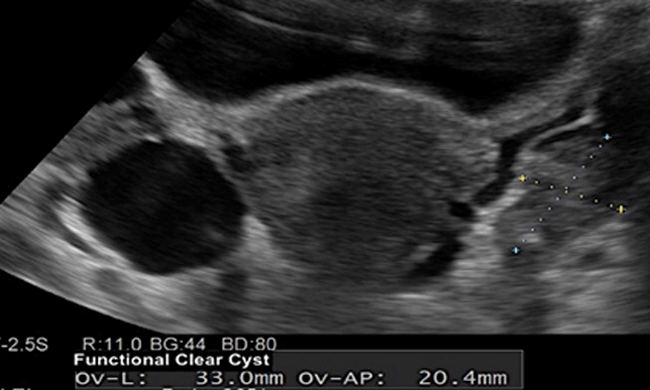

“水囊”或功能性卵巢囊肿是育龄期最常见的囊肿。功能性囊肿是正常排卵功能的结果。它们只含有液体,通常会在一两个月内消退,因此很少需要治疗。囊肿通常小于 5 厘米,但有时也会大至 8 厘米。